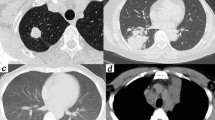

Chest CT was performed in all these patients. The imaging manifestations were diverse, as shown in Fig. 1. Table 3 shows the details of chest CT findings in immunocompromised and immunocompetent patients. The most common manifestations were pulmonary nodules (93/136, 68.4%) and patchy shadows (56/136, 41.2%). Multiple pulmonary nodules, ground-glass attenuation/interstitial changes and cavitation were more common in immunocompromised patients (P <0.05). The involvement rate of bilateral lungs was 57.4% (78/136), which mostly involving left lower lung. Lesions were more likely to involve bilateral lungs in immunocompromised patients (P <0.05). A total of 47 patients were misdiagnosed as tuberculosis or tumor. Immunocompromised PC patients were more likely to be misdiagnosed as tuberculosis than immunocompetent patients, and tumor was more likely to be considered in immunocompetent patients, but there was no significant difference (P >0.05).

The findings of chest computed tomography of pulmonary crypotoccosis (immunocompetent patients: (a–e); immunocompromised patients: (f–h): (a) ground glass attenuation; (b) a single small nodule; (c) multiple lung nodules; (d) patchy shadows with air bronchogram; (e) nodular shadow with spiculate boundary; (f) pulmonary cavity; (g) scattered irregular patchy consolidation, nodules and mass shadows in bilateral lungs, and formation of cavities in a few lesions; (h) shadows of miliary nodules in bilateral lungs.